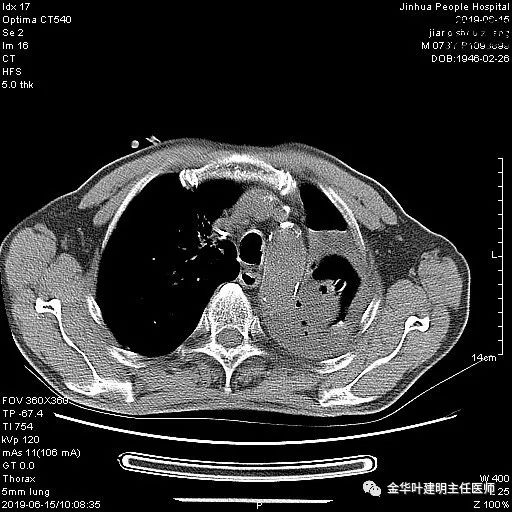

考虑左侧大量胸腔积液,遂进一步胸部CT检查:

以上是肺窗表现,下面为纵隔窗影像: